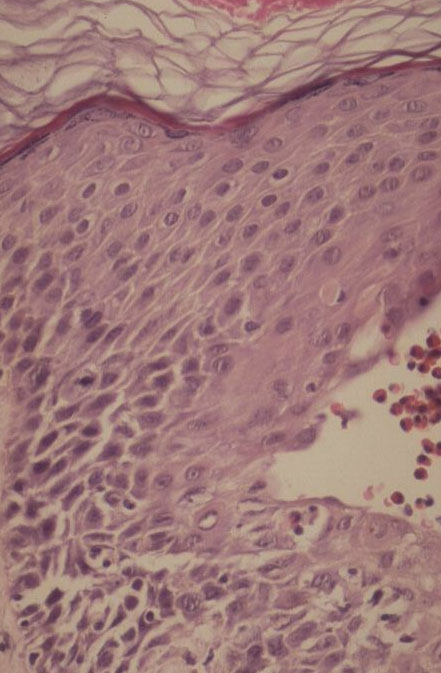

The alterations in the second stage consist of acanthosis, irregular papillomatosis, and hyperkeratosis. Intraepidermal keratinization, consisting of whorls of keratinocytes and of scattered dyskeratotic cells, is often more pronounced than in the first stage. The basal cells show vacuolization and a decrease in their melanin content. The dermis shows a mild, chronic inflammatory infiltrate intermingled with melano-phages. This infiltrate extends into the epidermis in many places.

The vesicles seen during the first stage arise within the epidermis and are associated with spongiosis. They are of the type seen in dermatitis . However, they differ from the vesicles of dermatitis by the numerous eosinophils within them and around them in the epidermis (eosinophilic spongiosis) . The epidermis between the vesicles often shows single dyskeratotic cells and whorls of squamous cells with central keratinization. Like the epidermis, the dermis shows an infiltrate containing many eosinophils and some mononuclear cells.